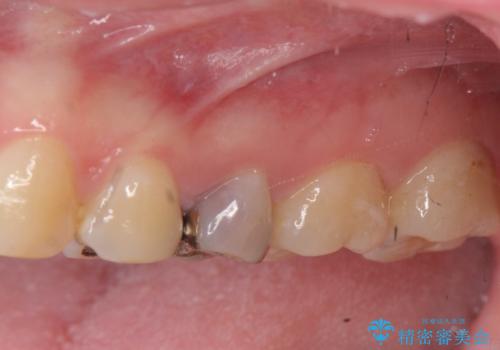

放置された虫歯 小矯正+歯周外科による保存処置